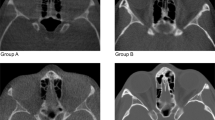

All radiographic scans were performed by professional radiologists under standardized conditions regarding the water embedding process and the anatomical form stability of the specimens. Corresponding slices from radiographic volumes of one skull, through each acquisition setting, are provided in Supplementary Fig. 2.